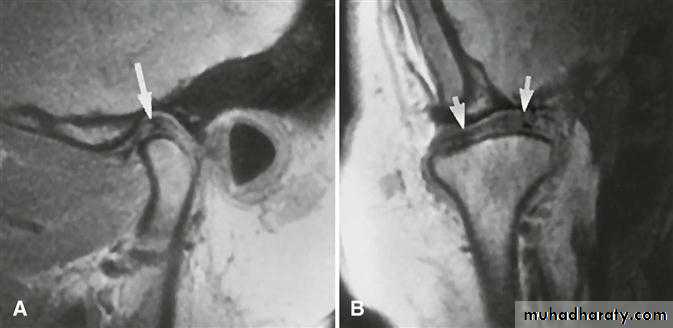

A clinical diagnosis of suspected internal derangement might lead to a requirement for imaging of the disc. This is done by magnetic resonance imaging (MRI).

No abnormalities are apparent on plain radiographs. MR imaging shows the displaced disc in a closed/ rest position ( nothing is indicative, but real time MRI) is helpful.

Radiology

Plain films usually show nothing. In long- standing cases, there may be signs of osteoarthrosis.

MRI shows an abnormal disc position in all movements.

In long standing cases, perforation of the disc may be seen and joint space adhesions inferred.